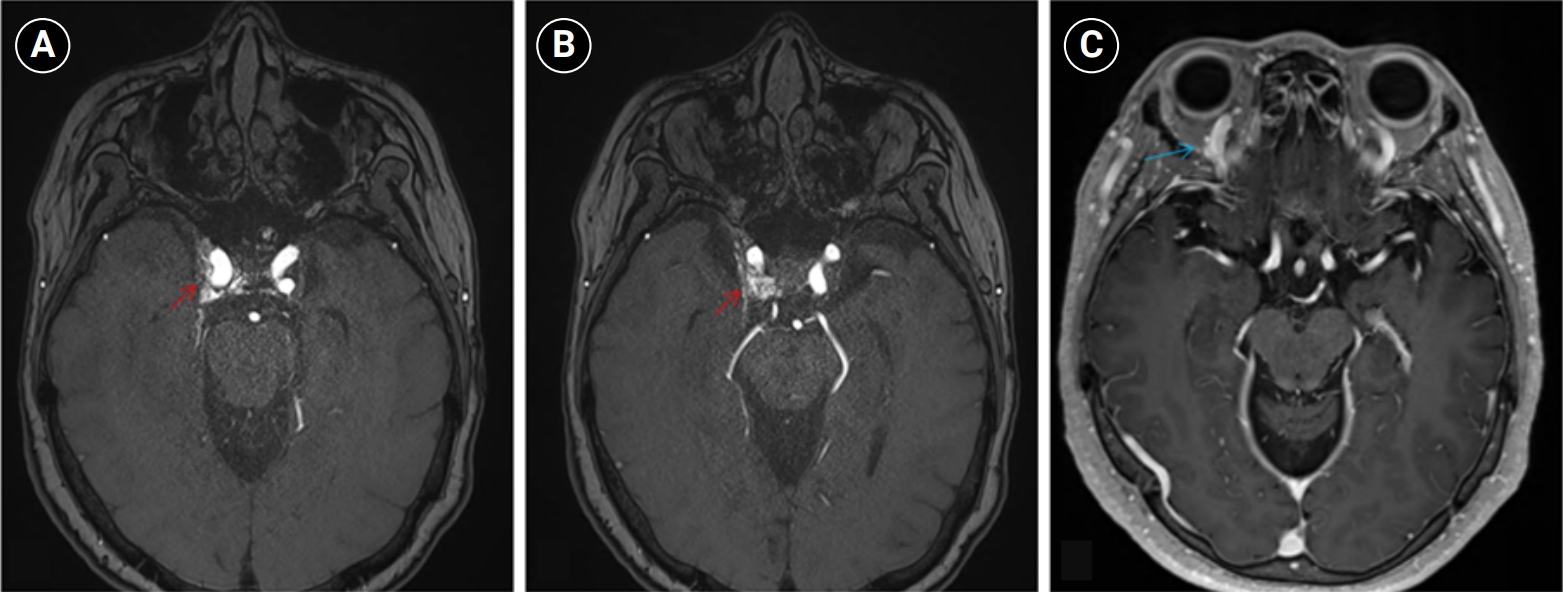

Baseline hematology and chemistry—including complete blood count, electrolytes, renal/hepatic indices—and coagulation tests (prothrombin time/international normalized ratio, activated partial thromboplastin time) were within reference limits. Erythrocyte sedimentation rate and C-reactive protein were normal. A focused screen for secondary trigeminal neuropathy (thyroid-stimulating hormone, vitamin B12, HbA1c) was negative. There were no clinical signs of infection. Brain magnetic resonance imaging (MRI) demonstrated high flow related signal in the right cavernous sinus and asymmetric dilation of the superior ophthalmic veins (right>left), raising suspicion for a CCF (Figure 1). Definitive diagnosis was established on digital subtraction angiography (DSA), which identified a right CCF. DSA demonstrated an indirect CCF supplied by the right meningohypophyseal trunk of the ICA and by right ECA branches, including the internal maxillary artery and the cavernous branch of the middle meningeal artery, consistent with Barrow type D (Figure 2).6 Barrow type D denotes an indirect, low-flow fistula with dual ICA/ECA dural supply; unlike direct type, indirect types present more insidiously, and symptom patterns are largely determined by venous drainage, with posterior drainage often manifesting as CN VI palsy and headache (Table 1).1,3,6,7 The fistula was treated with transvenous Onyx embolization. On post-procedure day 1, non-contrast time-of-flight magnetic resonance angiography (TOF-MRA) demonstrated a marked reduction of flow related hyperintensity within the right cavernous sinus, and the right superior ophthalmic vein caliber decreased from 6.63 to 4.61 mm (Figure 3A, B). Follow-up DSA (at 3 weeks) likewise showed substantial attenuation of fistulous opacification (Figure 3C), supporting a significant interval decrease in arteriovenous shunting. At 1–2 weeks, the patient reported an ~80%–90% reduction in dental/lower-facial pain and bifrontal headache from NRS 7–8 to 1–2. By 1 month, red-glass testing demonstrated resolution of primary-position diplopia. Formal prism measurements were unavailable; bedside ocular-motor grading was recorded using a standard duction underaction scale (–4 to 0). Right abduction improved from –1 to 0, and primary-position diplopia was absent at distance and near, consistent with recovery from abducens palsy.

Figure 2.Digital subtraction angiography findings in the patient. (A) Right internal carotid artery (ICA) angiogram shows an indirect carotid-cavernous fistula supplied by the meningohypophyseal trunk of the cavernous ICA (black arrow). (B, C) Right external carotid artery angiogram demonstrates additional arterial supply from external carotid branches, including the internal maxillary artery (blue arrows) and the cavernous branch of the middle meningeal artery (red arrows).